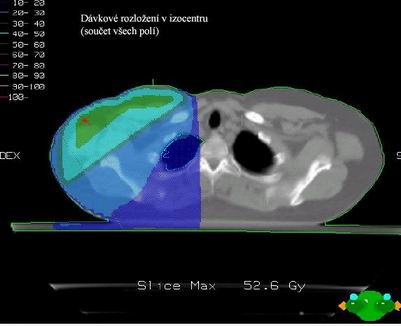

Dvě tangenciální hrudní pole

většinou s klíny

A jedno přímé pole nadklíček + boost axilla Pa pole (8 Gy)

Společné izocentrum pro všechna pole